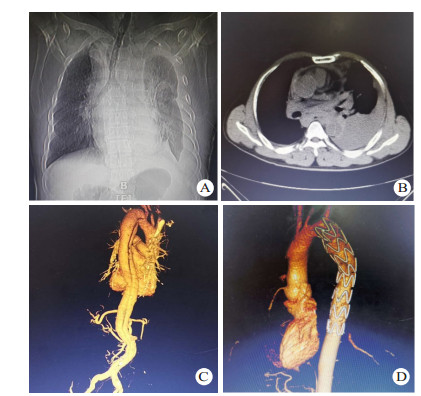

2 结果13患者接受TEVAR。11例夹层破口位于胸降主动脉峡部,2例夹层破口位于降主动脉中段; 累及左侧锁骨下动脉2例,左侧锁骨下动脉开口周围血肿1例; 合并迷走右锁骨下动脉1例(图 3)。破口距离左侧锁骨下动脉开口距离0~51 mm,(30.14±14.85)mm,累及左侧锁骨下动脉2例及左侧锁骨下动脉开口血肿1例患者完全覆盖左侧锁骨下动脉; 2例患者因破口距左锁骨下动脉开口距离近,锚定区不足,覆盖1/2左锁骨下动脉; 1例患者因合夹层累计左侧锁骨下动脉且合并迷走右锁骨下动脉,在手术室先行左侧颈总动脉-左侧锁骨下动脉、右颈总动脉-右锁骨下动脉转流,然后再到介入室行TEVAR手术并覆盖左侧锁骨下动脉。全组主动脉内径27~35 mm,(32.1±3.7)mm,所选择支架直径比CT所测锚定区直径大15%。TEVAR手术时间55~ 129 min,(83.2±21.3)min。本组手术患者死亡1例,病死率为7.7%,死亡原因为合并多根多处肋骨骨折所致呼吸衰竭,1例患者术中造影发现I型内漏,采用高压球囊扩张后内漏消失,其余患者经过治疗后均痊愈出院,住院时间(13.8±6.9)d。出院后失访1例,其余患者均随访1~4年,无支架移位、内漏、截瘫、缺血性脑卒中、左上肢缺血及新发夹层或动脉瘤等并发症,均恢复正常生活。

| 图 3 患者56岁,因车祸伤入院,入院后诊断TAD合并迷走右锁骨下动脉(A:胸部增强CT提示降主动夹层,右侧锁骨下动脉起源于降主动脉,沿食管后方走行,左侧胸腔大量血胸,右侧纵隔积血,B:胸腹部CTA提示降主动脉夹层,夹层累及迷走右锁骨下动脉) |

怀疑或诊断急性创伤性Stanford B型主动脉夹层患者应立即予以维持生命体征,将收缩压控制在110~120 mmHg,心率控制在60~80次/min。手术是急性创伤性Stanford B型主动脉夹层唯一确定有效的治疗方法。传统的手术方式为开放手术,需在体外循环下行主动脉修补或人工血管置换。此类手术时间长,操作复杂,出血量大,术后并发症发生率、病死率较高; 加之此类患者常合并严重的其他脏器或组织损伤,体外循环时肝素化可能加重出血,增加手术风险。研究报道,开放手术术后截瘫发生率高达13%,围手术期病死率为24%[14]。与传统手术相比较,腔内修复具有创伤小、手术时间短、恢复快、并发症少等优点,逐渐广泛应用于临床。研究表明,腔内修复术可明显降低心脑血管事件、截瘫、肺部感染、肾功能衰竭的发生率及近期病死率[15]。对于急性创伤性Stanford B型主动脉夹层,腔内修复是一种切实可行的治疗方法[16-17],其避免了体外循环的并发症及肝素化的出血,这一点对于夹层合并其他脏器损伤时尤为重要。本研究结果显示,急性创伤性Stanford B型主动脉夹层是TEVAR的绝佳适应证。与自发性主动脉夹层相比,急性创伤性Stanford B型主动脉夹层累及范围相对局限,血管条件较好,上下均为正常血管,为支架提供了良好的附着点和锚定区[18]。对于急性创伤性Stanford B型主动脉夹层行TEVAR,笔者建议夹层破口区应距左侧锁骨下动脉10 mm以上,以提供足够的锚定区; 但对于锚定区不足10 mm者并不是TEVAR的禁忌证,可以通过覆盖部分或全部左侧锁骨下动脉以获得足够的锚定区,多数病例左侧锁骨下动脉封闭后可通过侧枝循环重新供血,不会影响左上肢功能; 本组病例中3例完全覆盖左侧锁骨下动脉,2例覆盖部分左侧锁骨下动脉,均未发生左上肢缺血及缺血性脑卒中等并发症。若患者为左椎动脉优势型,应尽量避免完全覆盖左侧锁骨下动脉以减少脑部缺血并发症,可先行烟囱技术、开窗技术或左侧颈总动脉-左侧锁骨下动脉转流,再行TEVAR。对于Stanford B型主动脉夹层合并迷走右锁骨下动脉病例,若夹层累及左侧锁骨下动脉或距左侧锁骨下动脉距离较近,应先行双侧颈总动脉-锁骨下动脉转流,再行TEVAR; 若距左锁骨下动脉有足够的锚定区,则判断其是左侧椎动脉优势型还是右侧椎动脉优势型,若为左椎动脉优势型,可不转流,若为右椎动脉优势型,则行右侧颈总动脉-右侧锁骨下动脉转流; 同时,夹层合并迷走右锁骨下动脉患者均需使用弹簧圈栓塞迷走右侧锁骨下动脉开口以减少术后内漏发生。本组病例中1例患者因创伤性Stanford B型主动脉夹层合并迷走右锁骨下动脉且夹层累及左侧锁骨下动脉开口,行双侧颈总动脉-锁骨下动脉转流,并使用弹簧圈栓塞迷走右侧锁骨下动脉开口。TEVAR并发症主要有内漏、截瘫、缺血性脑卒中、左上肢缺血、支架移位等。为减少内漏的发生,应保证足够的锚定区,选择支架型号应大于主动脉内径的15%~20%[19],释放支架过程中应将收缩压严格控制在120 mmHg以下。覆膜支架长度选择以能完全覆盖瘤体破口即可,应尽量避免支架下缘达胸8水平,以减少脊髓缺血及截瘫发生。颈总动脉-锁骨下动脉转流能为TEVAR并发缺血性脑卒中和左上肢缺血提供有力保障。本组病例中1例患者术中造影发现Ⅰ型内漏,采用高压球囊扩张后内漏消失。其余患者在随访期间均未发生上述并发症,能正常生活。